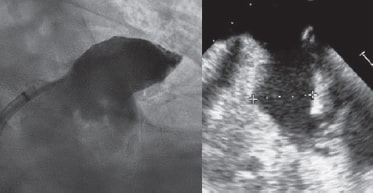

Varón de 80 años con fibrilación auricular permanente (consentimiento informado obtenido) tratado con una intervención percutánea de cierre de la orejuela izquierda (OI). Había ingresado repetidas veces con un cuadro de anemia grave y hemorragias gastrointestinales crónicas mientras estaba en tratamiento con diferentes regímenes antitrombóticos (ácido acetilsalicílico, clopidogrel, apixabán). Tenía una puntuación de 6 en la escala CHADS-VASC2 y de 4 en la escala HAS-BLED. La ecocardiografía transesofágica (ETE) confirmó la presencia de morfología en manga de viento con ausencia de trombo en la OI. Los diámetros de la zona de aterrizaje eran entre 23 y 25 mm (figura 1).

Figura 1.